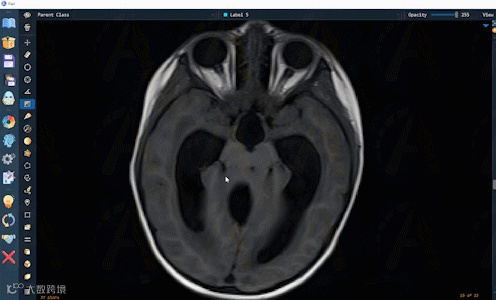

AutoSeg已在CT,MRI,超声,X-ray,PET,扫描电镜,病理,涂片,内窥镜等影像模态的多种解剖结构和病灶上验证和使用。AutoSeg的标注结果可便捷编辑修改,以方便用户微调和快速确认。如下是AutoSeg在多样化的影像和解剖结构上的应用展示: